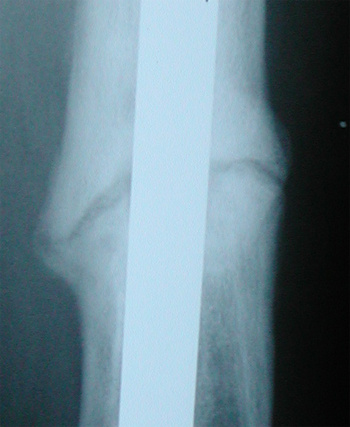

May. 5, 2005 X-ray update

Left to right if you have a wide screen, or top-to-bottom with a narrow screen, are three months (Jan, 5), 5 months (Mar. 1), and 7 months (May 5). Average healing time is 8.2 months or somelike like that. It was okay then got a little worse then got a little better. It feels better each time though, so that is seen as a good sign...such as it is.